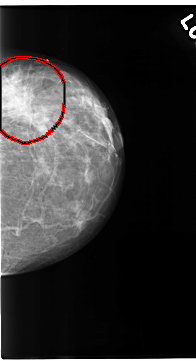

C_0123_1.LEFT_MLO

LEFT_MLO LINES 4688 PIXELS_PER_LINE 2424 BITS_PER_PIXEL 12 RESOLUTION 50 OVERLAY

FILE: C_0123_1.LEFT_MLO.OVERLAY

TOTAL_ABNORMALITIES 1

ABNORMALITY 1

LESION_TYPE MASS SHAPE IRREGULAR MARGINS ILL_DEFINED

ASSESSMENT 5

SUBTLETY 5

PATHOLOGY MALIGNANT

TOTAL_OUTLINES 1

BOUNDARY